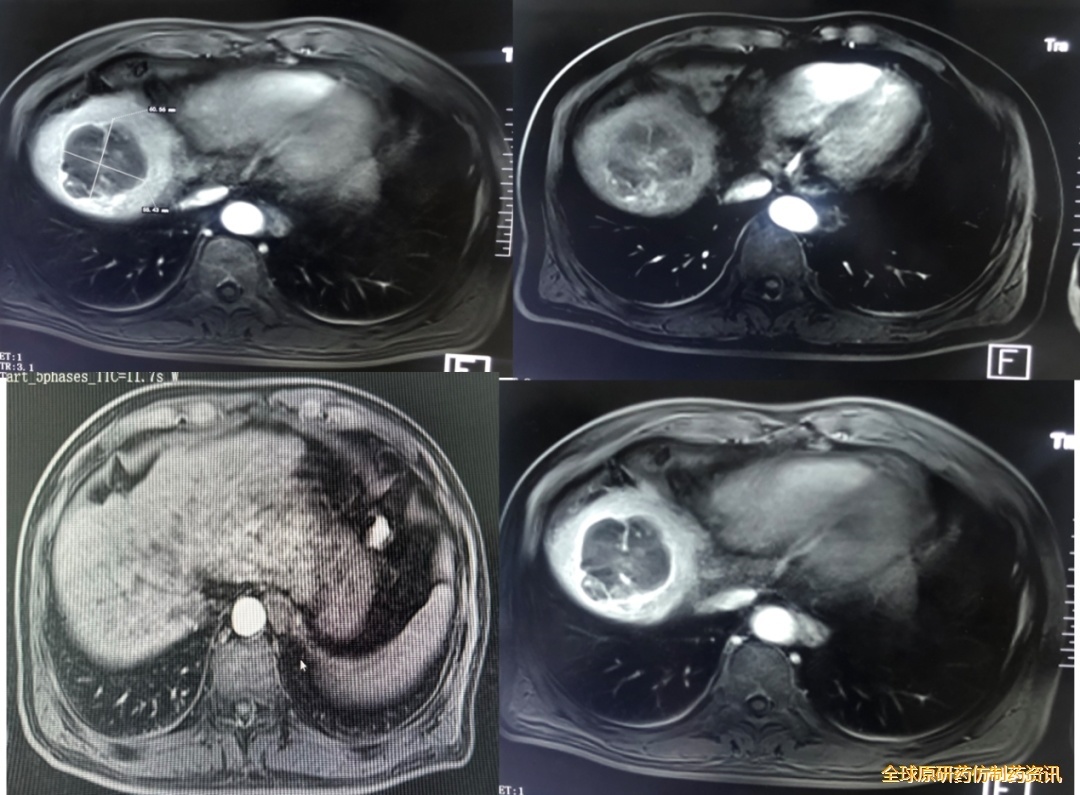

肝脏MRI(2021.4.2):肝恶性肿癌病史,对比2021.2.21片,肝脏体积缩小,肝裂增宽,边缘欠光整,肝后叶顶部仍见一团块状稍长T1稍长T2信号,其内可见分隔,反相位可见信号减低,DMI呈稍高信号,增强扫描显示动脉期可见不均匀强化,门脉期及延迟期较前减退,大小约58mm×69mm;另增强扫描扫描示肝实质内见多发结节状导常强化影,较大者直径约15mm,平扫未见明确显示。

腹部MRI(2021.4.2):门静脉增宽,直径约16mm,胆囊体积正常,壁不厚,腔内呈短T1长T2信号改变,囊内可见小结节样充盈缺损,胰腺形态、大小可,未见明显异常密度影;脾脏体积增大;肝脾周围可见线样长T2信号影;腹膜后见稍大淋巴结。

图2 2021.4.2影像学复查

目前诊断:原发性肝癌 Ib期(PS评分:0-1分;Child-Pugh分级:A级);乙肝肝硬化,门脉高压